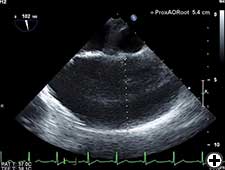

Ascending aorta dilatation should be confirmed with CT scan, aortography, or TOE.

- Choose an appropriate diameter Dacron tube graft, for example, 1.5-2 cm less the diameter of ascending aorta. In this patient we used 3.8 cm Dacron tube graft when proximal and distal ascending aorta were 5.4 cm and 5.69 cm respectively on preoperative TOE (Figures 3 & 4).